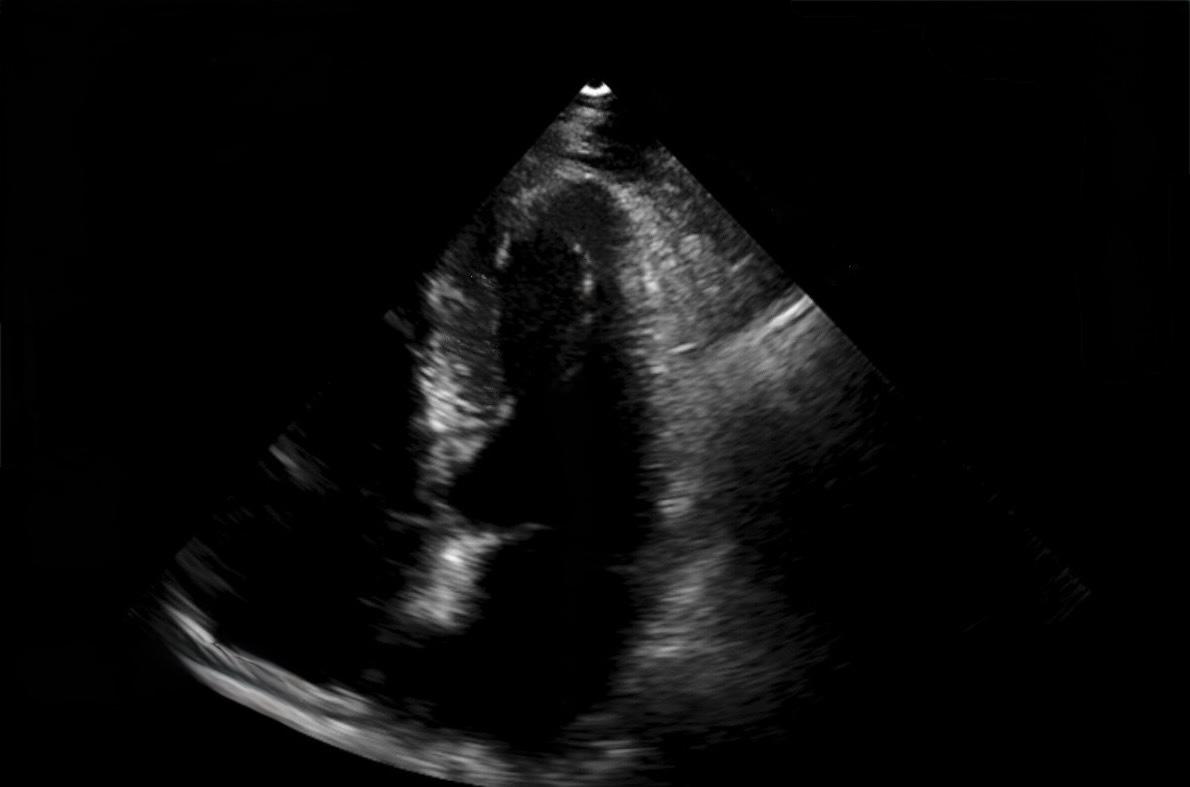

Bei einem 57-jährigen Patienten mit metastasiertem klarzelligem RCC zeigten sich in der CT-Verlaufskontrolle zwei neue, kontrastmittelanreichernde Läsionen im Myokard anteroapikal und septal, die differenzialdiagnostisch nicht sicher zwischen Thromben und Metastasen zu unterscheiden waren. Der Patient berichtete über Palpitationen, jedoch keine Dyspnoe oder Thoraxschmerzen. Das EKG ergab T-Wellen-Negativierungen in den Ableitungen V1–V6, NT-proBNP war mit 1670 pg/ml erhöht. Die transthorakale Echokardiographie zeigte eine fokale Wandverdickung anteroapikal und inferoseptal bei scharfer Abgrenzung des Endokards. Die linksventrikuläre Ejektionsfraktion lag bei etwa 55 %, Auffälligkeiten des rechten Ventrikels bestanden nicht. Zur differenzialdiagnostischen Abgrenzung erfolgte eine Kontrastechokardiographie, in der beide Läsionen eine deutliche Hypervaskularisation zeigten. Dieser Befund legte eine metastatische Genese nahe und war nicht mit dem avaskulären Erscheinungsbild thrombotischer Strukturen vereinbar. Aufgrund der Tumorprogression erfolgte ein Wechsel der systemischen Therapie von Sunitinib auf Belzutifan. Unter fortlaufender kardioonkologischer Betreuung ist der Patient derzeit klinisch stabil.